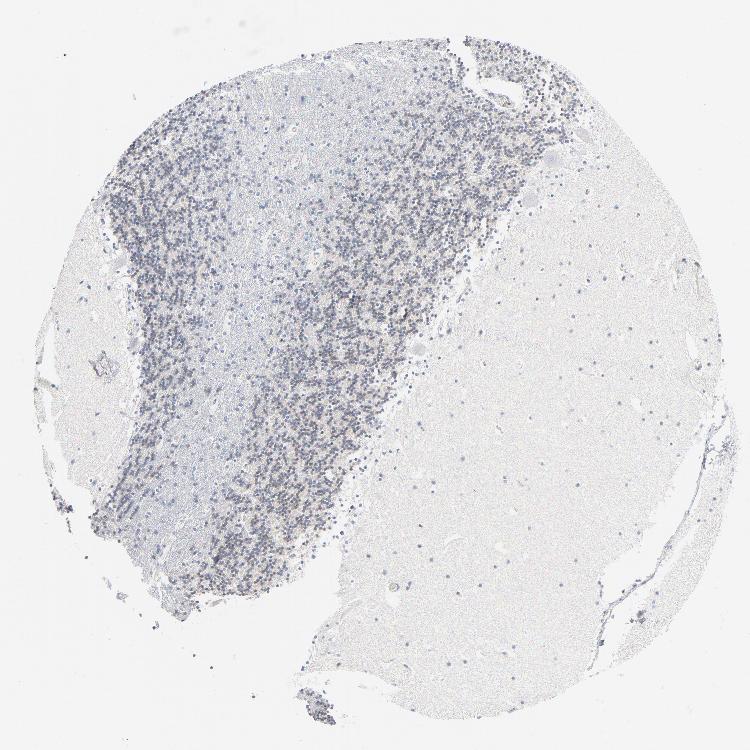

CEREBELLUM - Antibody stainingi

Antibody staining in the annotated cell types in the current human tissue is reported as not detected, low, medium, or high, based on conventional immunohistochemistry profiling in selected tissues. This score is based on the combination of the staining intensity and fraction of stained cells.

Each image is clickable and will lead to virtual microscopy that enables deeper exploration of all samples and also displays staining intensity scores, fraction scores and subcellular localization as well as patient and tissue information for each sample.

Antibody HPA026091Antibody HPA026276Antibody CAB003850

Purkinje cells MediumMediumNot detected

Cells in granular layer MediumNot detectedNot detected

Cells in molecular layer LowLowNot detected